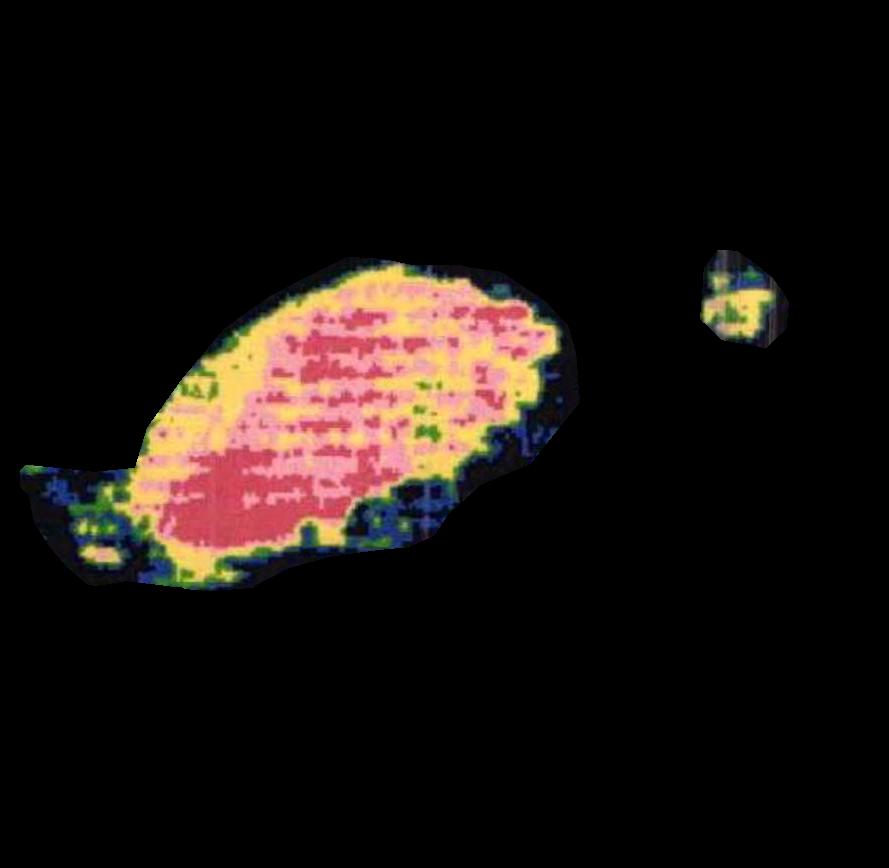

The LDI dataset includes a 2D colour image and a scan that shows the severity of burns and their complementary healing potential (HP) using a color palette. This smaller dataset consists of a total of 184 skin burn images and their associated LDI scans. The images of this smaller dataset belong to three different burn depth/degree classes as follows; 114 SPT images, 49 DPT images, and 21 FT images. The LDI scans were captured using the moorLDI laser Doppler imager (Moor Instruments Ltd) which is a non-invasive imaging device.

In order for the LDI scans to be comparable with BAM binary segmentations, a number of processing steps were conducted. LDI scans can have different sizes, scales, and cropping in comparison to their corresponding burn images. As BAM uses the burn 2D colour images as the input for creating the binary burn segmentations, the LDI scans were first aligned with their corresponding burn images and converted into the same size as those images. Once the LDI scans are aligned with input images and their colors are processed in order to create binary masks, quantitative comparisons with BAM segmentations were conducted. For this purpose, we utilised the manual segmentations of burn areas from burn images validated by clinicians.

Moreover, as discussed later, it was discovered that the LDI scan color palette, which demonstrates different healing potentials, would classify uninjured areas and background noise in the image as burns with poor blood flow. In a clinical setting, this misclassification does not lead to a serious issue as scans are reviewed by clinicians who can easily differentiate between normal skin/background and burn area. However, since the processing of LDI scans is conducted by computer vision, this issue needed to be resolved. This was addressed by removing the non-burn areas from the LDI scans before processing LDI scans by multiplying the aligned LDI scans with the manual segmentations of burn areas resulting in LDI scans that show various healing potentials (or various degrees of burn) in the burn area only.

4 Quantitative Analysis

We evaluated the performance of the BAM in segmenting burn areas from images using a dataset of manual segmentations validated by clinicians of burn areas from 2D colour images. We also compared BAM against Laser Doppler Imaging (LDI) results, the gold standard for assessing the depth and healing potential of burns. LDI generates a map of the blood flow in different parts of skin (including the burn areas) using laser Doppler technology. During scanning, laser light enters the skin tissue and is scattered by moving blood cells in the tissue. As a result, the frequency of the light changes according to the Doppler effect; the higher the speed and concentration of moving blood cells in a tissue, the higher the amplitude of the laser Doppler signal. This blood flow image is used to calculate three categories of healing potential for burn wounds; 1) less than 14 days, 2) 14 to 21 days, and 3) more than 21 days Med (2021)Hoeksema et al. (2009). The colors of a blood flow image and their corresponding healing potential categories are illustrated in Figure 6.